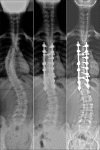

Background: Correcting the scoliosis and stabilizing the spine in the corrected position is the basis of treatment for adolescent idiopathic scoliosis (AIS). Spinal instrumentation and derotation are the principle steps of surgery for any type of AIS. A perspicuous understanding needs to be attained regarding derotation maneuvers in practice; therefore, we intend to compare radiological outcomes following concave and convex rod derotation maneuvers to analyze their efficacy to correct selective Lenke's Type-1 scoliosis.

Materials and methods: Retrospectively, 88 patients with Lenke's Type-1 scoliosis who were operated with selective thoracic instrumentation were divided into two groups depending on the derotation side. Preoperative radiographs were analyzed for curve angles, thoracic apical vertebral translation, apical vertebral rotation, and coronal/sagittal balance. Postoperative and followup assessment was focused on curve correction. Correction rate of main thoracic (MT) curve and its corresponding loss of correction at final followup are calculated.

Results: Concave group (n = 40; age 13.8 ± 1.9) and the convex group (n = 48; Age 14.3 ± 2.4) showed similar demographic characteristics. Postoperative and followup parameters showed no significant difference. Correction rate of MT curve between both groups (concave group = 69.2 ± 10.5%; convex group = 66 ± 12.8%; P = 0.20) was similar. There was minimal loss of correction at final followup among both groups (concave group = 2.2° ±5.4°; Convex group = 1.5° ± 4.8°; P = 0.52).

Conclusion: The study results showed similar sustained satisfactory correction of flexible Lenke's type 1 scoliotic curves irrespective of the derotation maneuver used. Adequate correction, thereby restoring balance was predominantly perceived among the entire sample. Hence, convex derotation can be considered equally effective as that of concave derotation for achieving adequate correction of selective Lenke's Type-1 scoliosis.